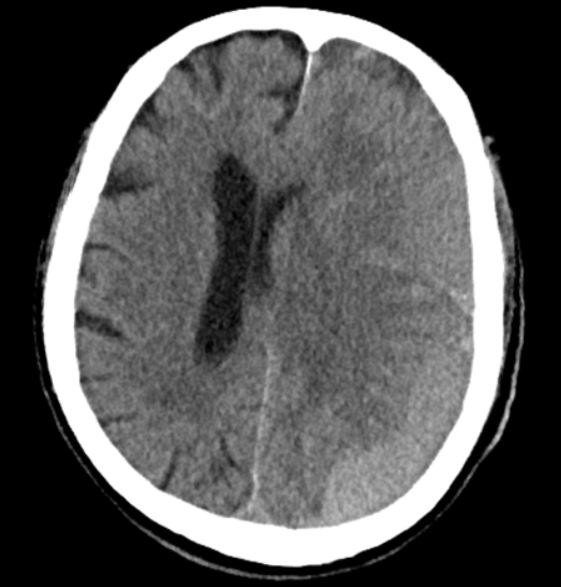

An 81 yo M presents to the ED with his daughter for worsening confusion. There is no reported trauma, but the patient is on anticoagulation. His physical exam is significant for expressive aphasia. A CT scan is obtained. What's the diagnosis? (scroll down for answer)

Answer: Acute on chronic subdural hematoma with mass effect

- Intracranial hemorrhage caused by venous bleeding into the potential space between dura and brain parenchyma

- Acute SDH: occurs within 14 days of injury and patients typically present after significant head trauma. On CT, appears as a hyperdense crescent shaped lesion that crosses suture lines

- Chronic SDH: after 14 days, often without history of traumatic event. On CT, are isodense, therefore more difficult to identify

- Chronic SDH is commonly seen in elderly patients or alcoholics and presenting complaint may be altered MS